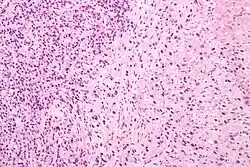

Gleason 4

Gleason pattern 4 glands are no longer single/separated glands like those seen in patterns 1–3. They look fused together, difficult to distinguish, with rare lumen formation vs Gleason 1–3 which usually all have open lumens (spaces) within the glands, or can be cribriform-(resembling the cribriform plate/similar to a sieve: an item with many perforations). Fused glands are chains, nests, or groups of glands that are no longer entirely separated by stroma-(connective tissue that normally separates individual glands in this case). Fused glands contain occasional stroma giving the appearance of "partial" separation of the glands. Due to this partial separation, fused glands sometimes have a scalloped (think looking at a slice of bread with bite taken out of it) appearance at their edges.[4][7]

Cytological differences between normal prostate and neoplastic glands are evident in changes to the typical two cell layers of the gland. In prostatic adenocarcinoma, the basal (bottom, usually cuboidal type) cell layer is lost, with only the top layer (usually columnar to pseudostratified) remaining.